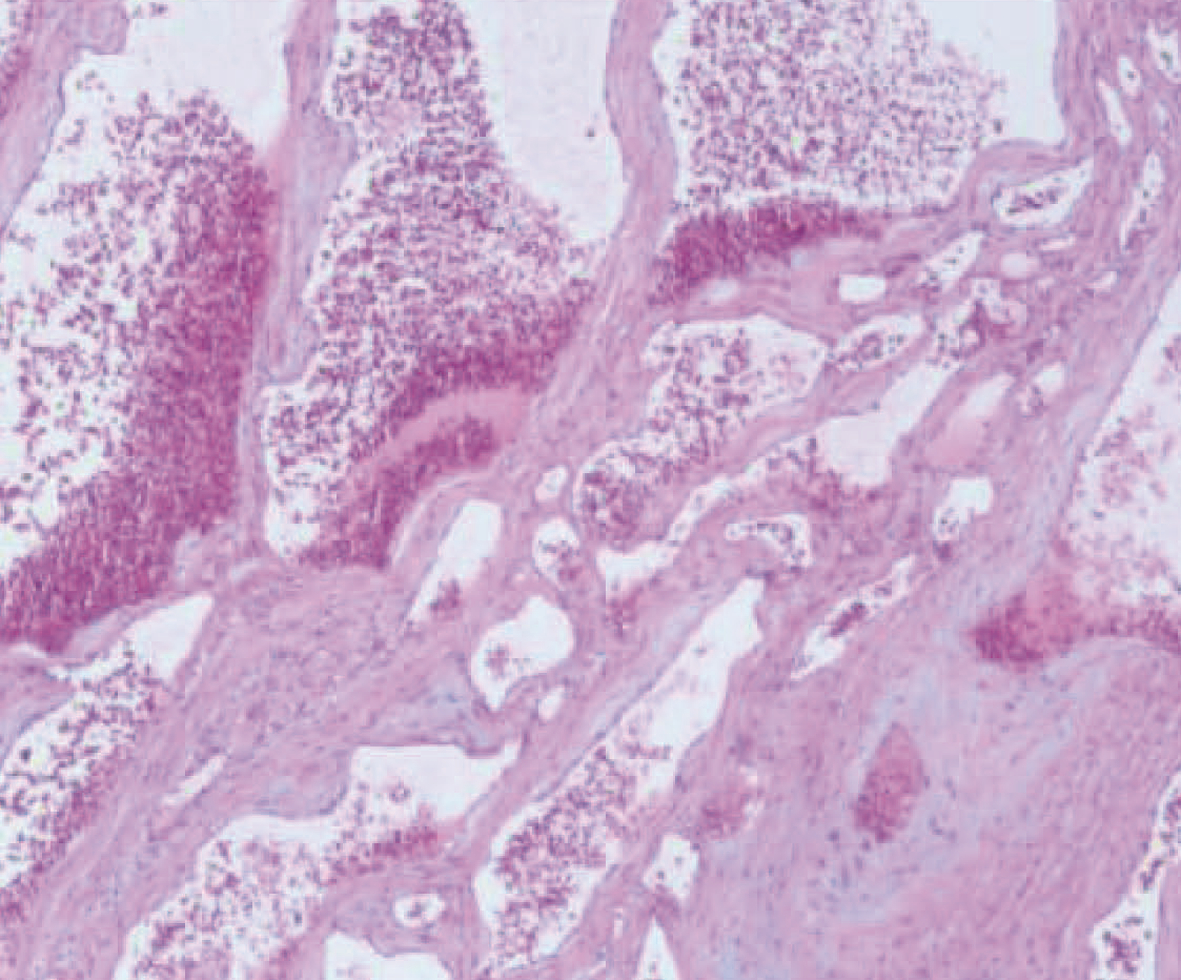

Association of P-I-R classification and Laennec grading with histology and prognosis after antiviral therapy in patients with hepatitis B cirrhosis

Caihong LYU, Zheng SONG, Jing LUO, Xiujuan CHANG, Yongping YANG

2023, 39(3): 580-589. DOI: 10.3969/j.issn.1001-5256.2023.03.015

Abstract(910) HTML (591) PDF (3408KB)(86)

Abstract:

Objective  To investigate the role of P-I-R classification and Laennec grading in evaluating histological changes in patients with hepatitis B cirrhosis after receiving antiviral therapy, as well as the association of these two evaluation systems with clinical prognosis.  Methods  A total of 218 patients from 14 centers were consecutively screened from October 2013 to October 2014, and these patients were diagnosed with liver cirrhosis based on pathology (Ishak score ≥5), received antiviral therapy for 72 weeks, completed two liver biopsies, and met the P-I-R classification criteria. The 218 patients were divided into non-hepatocellular carcinoma (HCC) group with 186 patients and HCC group with 32 patients. The chi-square test and the Fisher's exact test were used for comparison of categorical data between groups. For the comparison of HCC after antiviral therapy, the non-parametric Mann-Whitney U test was used for continuous variables, and for the comparison of P-I-R classification and Laennec grading, the non-parametric Kruskal-Wallis H test was used for continuous variables. Univariate and multivariate Cox regression analyses were used to calculate hazard ratio (HR) and 95% confidence interval (CI), and the Kaplan-Meier method was used to calculate the cumulative incidence rate of HCC.  Results  After 72 weeks of antiviral therapy, there was a significant difference in P-I-R classification between the non-HCC group and the HCC group (P < 0.001). There were significant differences in the distribution of Laennec grading and P-I-R classification before and after antiviral therapy (P < 0.001). After antiviral therapy, the 218 patients were divided into 4A group with 33 patients, 4B group with 71 patients, and 4C group with 114 patients according to Laennec grading, and there were significant differences between these three groups in platelet count (PLT) (H=36.429, P < 0.001), liver stiffness measurement (LSM) (H=13.983, P=0.004), Ishak score (χ2=23.060, P < 0.001), and HAI score (P < 0.001). After antiviral therapy, the 218 patients were divided into R group with 70 patients, I group with 52 patients, and P group with 96 patients according to P-I-R classification, and there were significant differences between these three groups in PLT (H=7.193, P=0.028), LSM (H=6.238, P=0.045), Ishak score (χ2=7.986, P < 0.001), HAI score (P=0.002), and HCC (P < 0.001). There was a significant difference in the incidence rate of HCC between the P and R groups based on P-I-R classification (HR=24.21, 95%CI: 0.46-177.99, P=0.002). After adjustment for other confounding factors, P-I-R classification was an independent predictive factor for HCC (HR=12.69, 95%CI: 4.63-34.80, P=0.002).  Conclusion  Both P-I-R classification and Laennec grading can reflect the features and changes of fibrosis before and after antiviral therapy, and P-I-R classification is more sensitive to fibrosis changes after antiviral therapy. P-I-R classification (after treatment) can be used to assess the risk of HCC in patients after antiviral therapy.